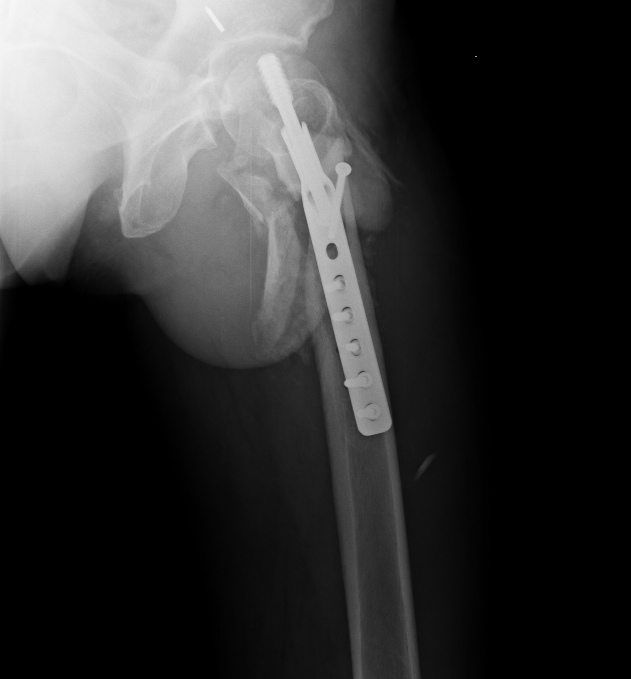

Спасибо за интересное обсуждение. Действительно, головка сохраняет сферичность, кровоснабжение ее должно быть сохранено, так что есть смысл сделать реконструкцию.

Удалили DHS, пришлось вытащить единым блоком, винт прокручивался. . Опознавательных знаков на имплантате не обнаружили. Дополнительный винт был введен во фрагмент, который оказался не связан ни с чем, так что удалили и его После удаления была хорошая подвижность. Сделали остеосинтез вот так. Комментарии и критика приветствуются.

Гвоздик 125 или 130гр.? Почему не 120? Почему не клинковая?

130 градусов. Как-то насчет 125 тут не знаю, чем бы он был более подходящий?

Клинковых пластин у нас принципе штук несколько есть, но длины клинков у них остались "неходовые". И посадочные долота какие-то страшные. Мы сейчас предпочитаем даже для вальгизирующих остеотомий гвозди - можно делать "открытый клин".